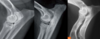

Fractures can be either..

A

primary or secondary.

Also, complete or incomplete. (periosteum can be intact with fracture line otherwise).

Left image: gunshot caused fracture.

Right image: osteosarcoma caused fracture.